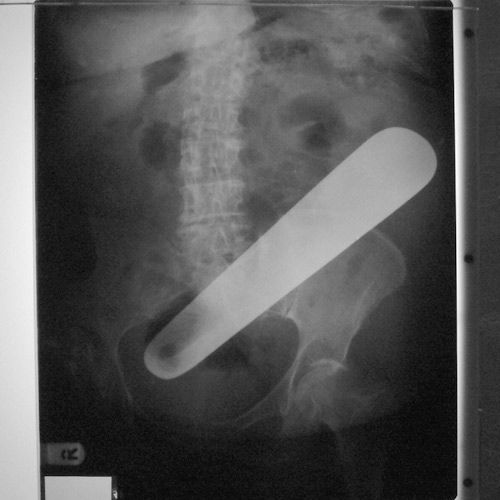

Под рентгеном